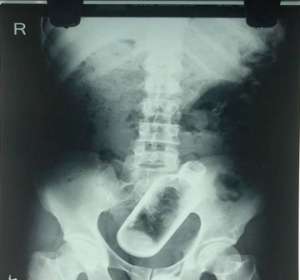

印度男子腹中有个酒瓶 竟是喝酒时吞下去的_0

印度36岁男子Narayan因为腹部和背部疼痛去医院检查,照完X光后在他的直肠部位发现了一个长达16厘米的酒瓶。 医生说,该男子来医院时声称自己时常觉...